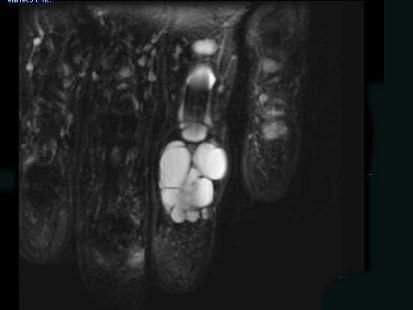

问题 女,77岁,发现右手部肿块二周,请结合影像图像提出最可能的诊断 ( )

选项 A、血管瘤 B、以上都不是 C、多发性腱鞘囊肿 D、骨囊肿 E、肌内脓肿

答案 C